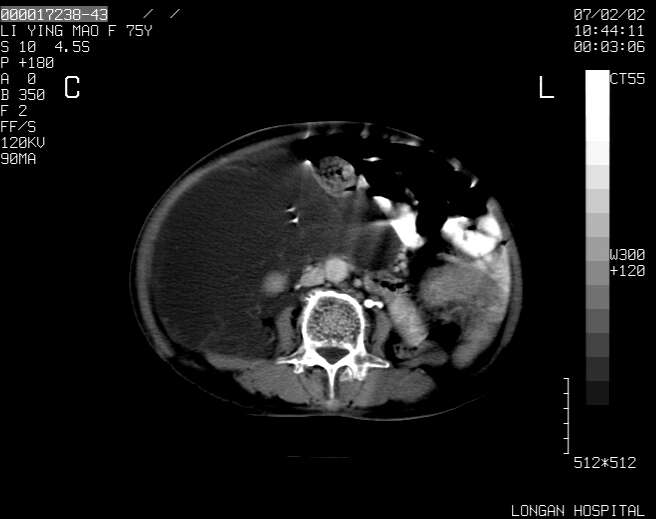

以下是引用dyqct在2007-2-10 8:53:00的发言:[br]考虑:1、肝脏多发囊肿[br] 2、左肾囊肿,右肾多发结石并积水。[br] 3、右胸少量积液。[br] 4、右肾周包裹性积液或淋巴管瘤(有见缝就钻的征象、薄隔、小结节状钙化)?[br] 5、腰椎动脉瘤样骨囊肿?[br] [br] [br]